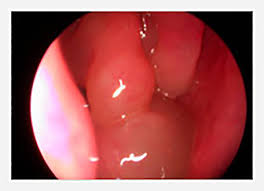

Nasal polyps are polyps in nasal cavity. They usually occur in both the right and left nasal passages and can block the flow of air. Learn about causes, polyp size, signs, and how to prevent colon cancer. Read about the symptoms, causes, treatments and when to see a nasal polyps are painless soft growths inside your nose. Polypoid polyps look like a mushroom, but flop around inside the intestine because they are attached to the lining of the colon by a thin stalk. Webmd explains nasal polyps, including what causes them, their symptoms, and their treatment. Symptoms include trouble breathing through the nose, loss of smell, decreased taste. Info about nasal polyps, cause and treatment of nasal polyps, homeopathic remedies and homeopathy treatment for nasal polyps.

Polypoid polyps look like a mushroom, but flop around inside the intestine because they are attached to the lining of the colon by a thin stalk. The most common symptoms of throat polyps are hoarseness, a deepening of the voice, or a breathy sounding voice. Small nasal polyps may cause no symptoms. This lump appears as a grape or teardrop inside the nasal passage. In most cases this is more of an annoyance than a real problem, but it is. They are not dangerous, but they should still be treated for the patient's comfort at least if they do cause discomfort. Nasal polyps are polyps in nasal cavity. Find out about nasal polyps, which are painless soft growths inside your nose.

Small nasal polyps may cause no symptoms. 8 colon polyps symptoms, pictures, types, causes, treatment. Larger growths or groups of nasal polyps can block your nasal passages or lead to breathing problems, a nasal polyps themselves are soft and lack sensation, so if they're small, you may not be aware you have them. Sometimes they grow large, though, and when they do they can develop ulcers. Nasal polyps are noncancerous growths of the tissues that line the nose and sinuses. Find out about nasal polyps, which are painless soft growths inside your nose. It is important to distinguish nasal polyps from neoplastic lesions, particularly if symptoms are. They are not dangerous, but they should still be treated for the patient's comfort at least if they do cause discomfort. Nasal polyps develops as a result of chronic inflammation in body and associated with health issues like allergies, asthma etc. A nasal polyp is a mass of gelatinous tissue which usually forms from allergy. Symptoms are due to the size and location of the polyps and associated mucosal inflammation; They are also usually triggered by chronic inflammation and are associated with a number of health conditions. Symptoms include trouble breathing through the nose, loss of smell, decreased taste, post nasal drip, and a runny nose.

Symptoms include trouble breathing through the nose, loss of smell, decreased taste, post nasal drip, and a runny nose. A nasal polyp is a mass of gelatinous tissue which usually forms from allergy. These are fleshy growths that arise from the small cavities (sinuses) or the lining of the nose. Nasal polyps (np) are noncancerous growths within the nose or sinuses. They usually occur in both the right and left nasal passages and can block the flow of air.